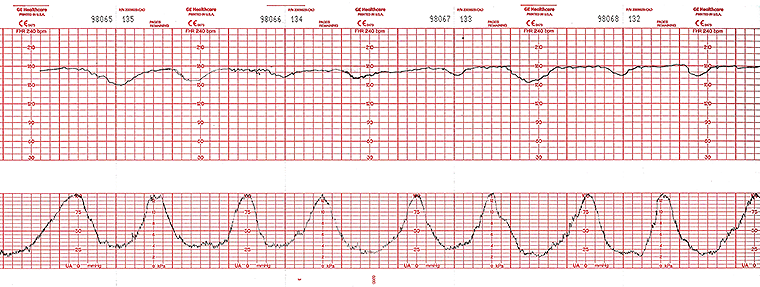

A 22-year-old woman, gravida 2, para 1, at 34 weeks’ gestation is admitted to the hospital 45 minutes after the sudden onset of vaginal bleeding and increasingly frequent episodes of abdominal pain, which has been increasing in severity. She has not had loss of vaginal fluid. She has received routine prenatal care. She has hypertension treated with labetalol. Her only other medication is a prenatal vitamin. Her previous pregnancy was uncomplicated and ended in spontaneous vaginal delivery of a healthy newborn at term. The patient appears uncomfortable. Temperature is 37.0°C (98.6°F), pulse is 110/min and regular, respirations are 16/min, and blood pressure is 150/85 mm Hg. Abdominal examination discloses diffuse tenderness to palpation. On pelvic examination, the uterus is consistent in size with a 30-week gestation. Fetal heart tracing is shown. Which of the following is the most appropriate next step in management?